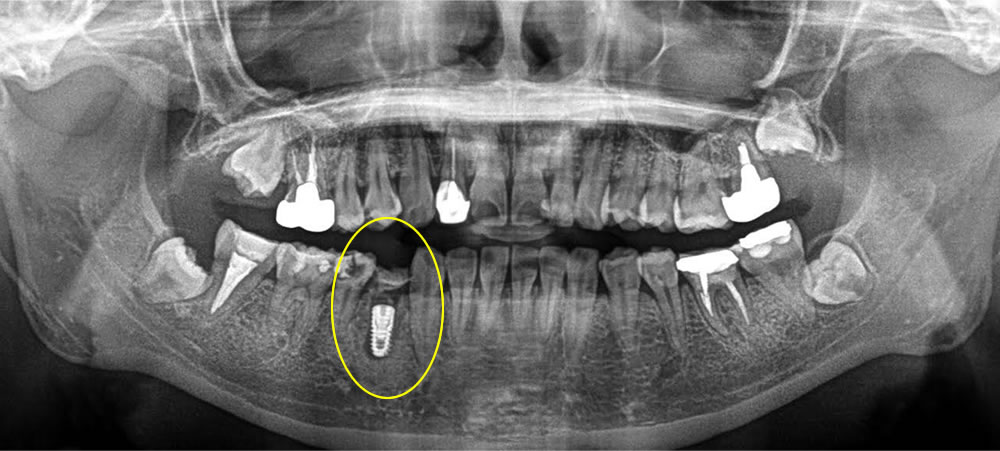

まず保存不可能な歯を抜いた後、中に溜まっている肉芽を全て除去し、即日でインプラント埋入を行い、骨の無くなっている所は骨を作る処置を行いました。しっかりと縫合し、歯茎に包帯のような物を付けて終了しました。この包帯は1週間後に除去し、糸は2週間後に取っていきました。

そこから4ヵ月間の待機後、しっかりと骨とインプラント体が結合している事を確認し、上部の歯を使っていきました。結果、咬合も回復し、綺麗な歯を作る事ができました。